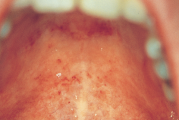

Punetised

Nakatumine – Inkubatsiooniaeg 14–21 ööpäeva – Nakkavus algab ca 2 päeva enne sümptomite ilmumist ning kestab nädala. Isoleerida 6 ööpäeva lööbe algusest.-Lööbeks on mõnemillimeetrise läbimõõduga roosad laigud, mis võivad laatuda ühtlaseks punetavaks alaks. Lööve algab